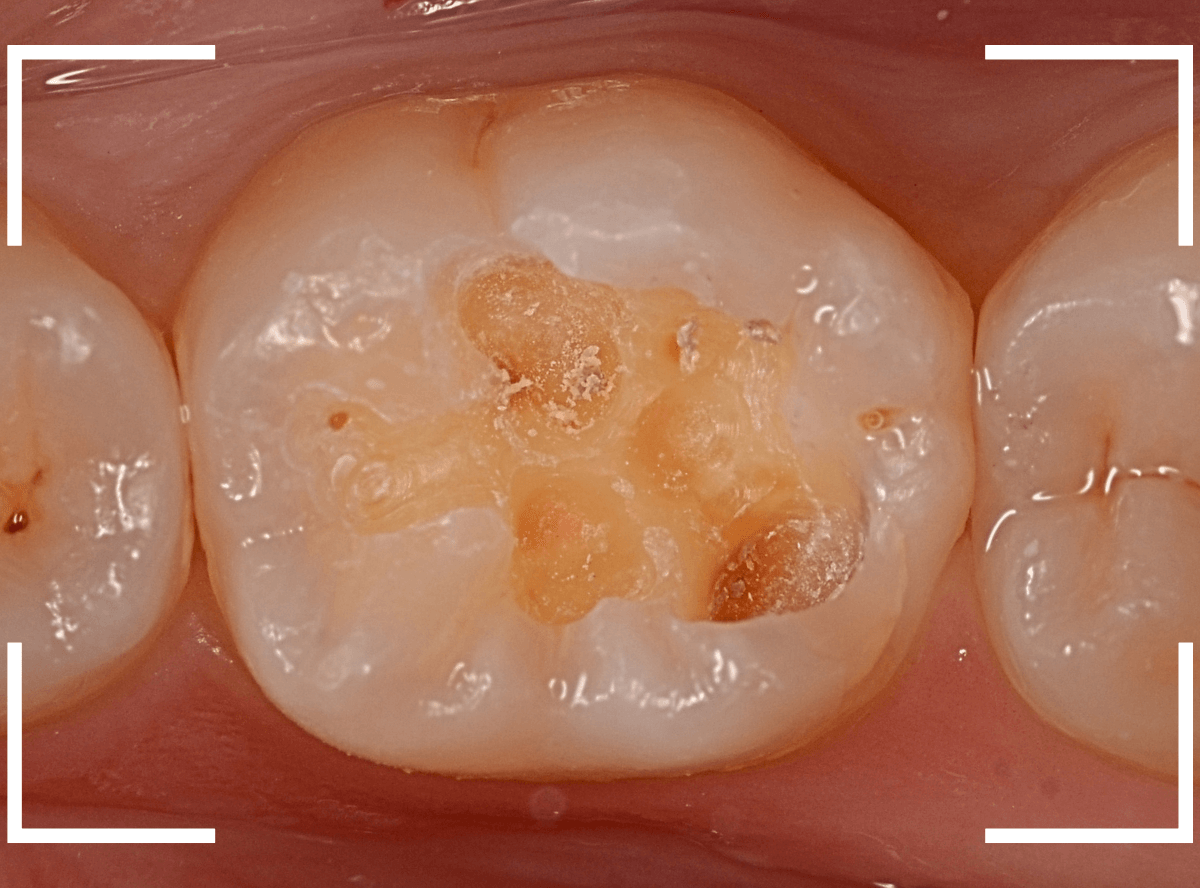

Case.8 大きな虫歯なのに、レントゲンではっきり写らない

こちらも定期検診希望で来院された患者さんです。

お口の中を拝見すると、明らかに虫歯がありました。

3本虫歯になっており、特に中央の小臼歯はかなり大きな虫歯になっているのが予想されます。

治療前にレントゲン写真で虫歯の大きさを確認するつもりが・・・あまりはっきり写ってきません。

患者さんに状況を説明して、歯を少しずつ削りながら虫歯を確認する事になりました。

まず、一番大きな虫歯と思われる部分を小さく削って確認します。

予想通り、虫歯が見えてきました。

隣りの奥歯と一緒に虫歯の治療を進めます。

色が染まっているところがまだ虫歯が残っている部分です。

2本とも、虫歯を全て取り切りました。

特に手前の歯はかなり広めの虫歯になっていました。

最終的に、手前の虫歯の除去も終わったところです。

手前の歯の虫歯は中央の歯まで達していました。

このように明らかに大きな虫歯があると診断されるような状況でも、レントゲン写真でうまく診断できない場合もあります。